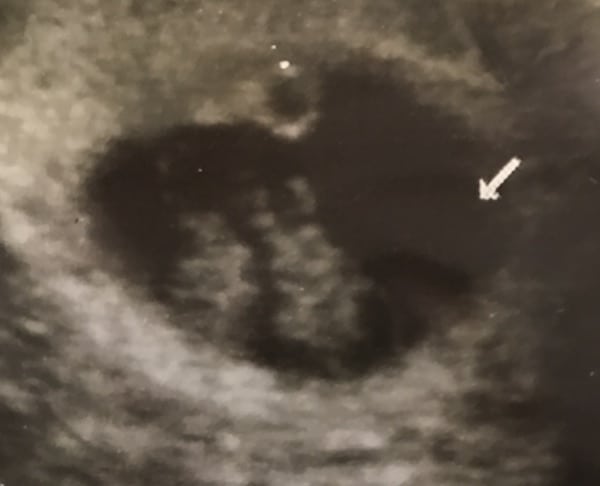

Ultrasound Photos – 8 Week Sonogram

8 week sonogra